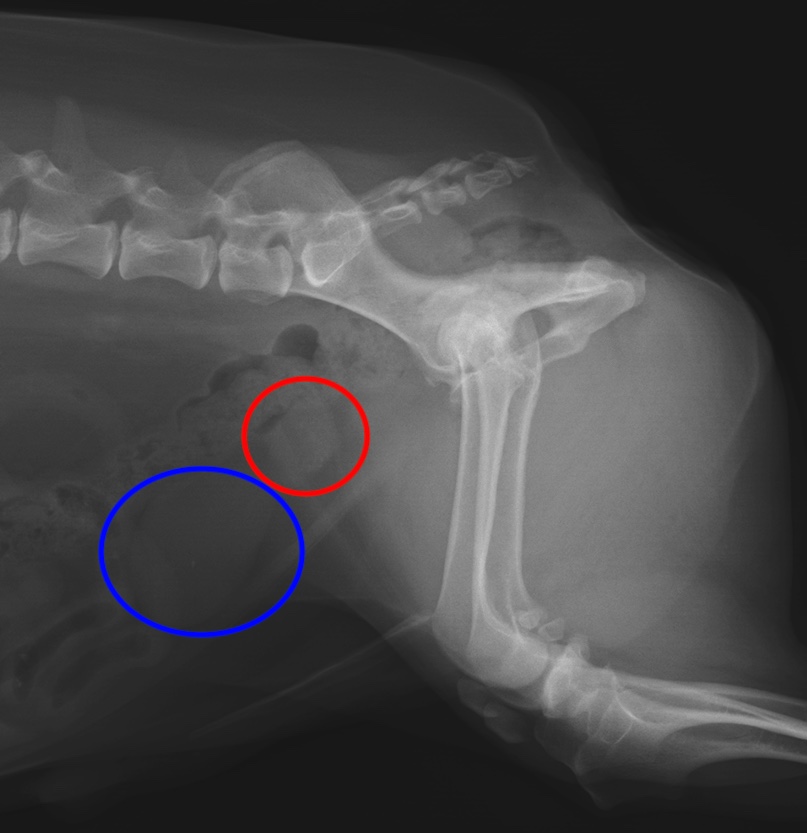

・レントゲン検査:前立腺の石灰化やリンパ節転移、遠隔転移(肺や骨など)の評価

前立腺癌のレントゲン画像(赤丸は石灰化した前立腺、青丸は膀胱)